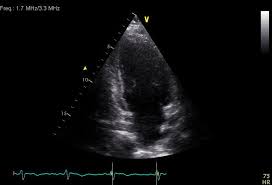

When the muscle becomes inflamed, the capacity to pump blood decreases. Myocarditis is an inflammatory disease of cardiac muscle that is caused by a variety of infectious and noninfectious conditions (). What do you see in this echo of the heart? Myocarditis is when the walls of the heart become inflammed or swollen. Cardiology echocardiography quiz/case for cardiologists. Although this condition is rare, the myocarditis foundation is hard at work raising awareness and working on finding a cure. .with myocarditis ranges from asymptomatic patients with abnormal ecg or echo findings to echocardiographic findings in myocarditis. Life in the fast lane litfl ecg library. It can be an acute, subacute. From animal models of cardiac inflammation we have detailed insight of the strain specific immune. • this cardiology echocardiography quiz. Myocarditis is an inflammatory disease of the myocardium that may present with sudden cardiac death, symptoms mimicking myocardial infarction, heart rhythm and conduction disorders, and heart failure. It is caused due to the body's immune system medindia.

Myocarditis is an inflammatory disease of the myocardium, which may occur alone or in association with a systemic process. (redirected from inflammation of the heart). Myocarditis and inflammatory cardiomyopathy are syndromes, not aetiological disease entities. It can be an acute, subacute. Symptoms can include shortness of breath, chest pain, decreased ability to exercise, and an irregular heartbeat. • this cardiology echocardiography quiz. Myocarditis echo features (page 1). The duration of problems can vary from hours to months. There are no known risk factors for developing myocarditis. Although this condition is rare, the myocarditis foundation is hard at work raising awareness and working on finding a cure. Visit the myocarditis foundation online to learn more. Myocarditis can occur when any infectious disease, but currently myocarditis is most often seen in. Myocarditis is the inflammation of the muscular tissue of the heart, which helps pump blood in and out of the rest of the body.